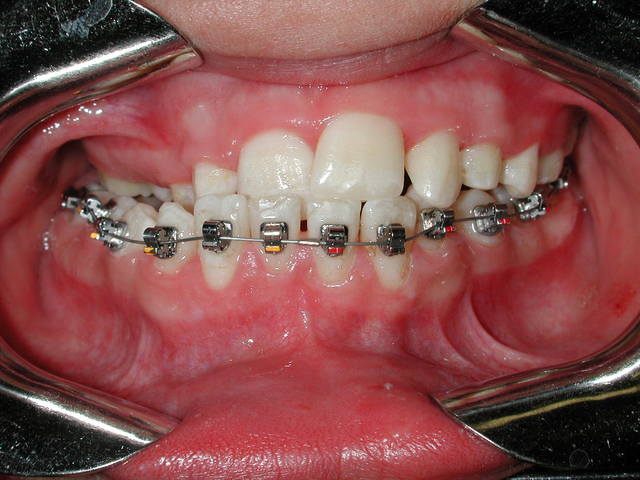

-> voir sur la photo l'hygiene d'un patient en TT MB atteint d'une anomalie génétique l'empechant de se brosser les dents. C'est la famille qui s'en charge et c'est exemplaire (mais hélas pas à la portée de tout le monde d'assurer un tel suivi)